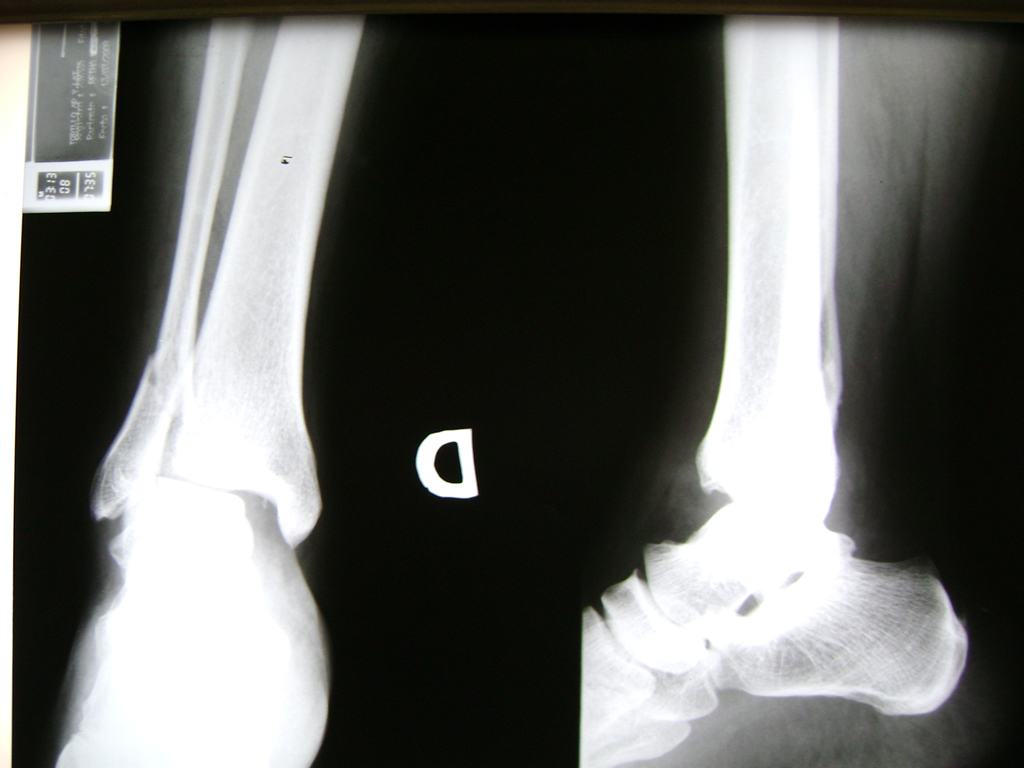

Una fractura de tobillo es la rotura de uno o más de los huesos del tobillo. Estas fracturas pueden ser:

- Parciales (el hueso está sólo parcialmente fisurado, no del todo).

- Completas (el hueso está perforado y está en 2 partes).

Algunas fracturas de tobillo pueden requerir cirugía si:

- Los extremos de los huesos están desalineados entre sí (desplazados).

- La fractura se extiende hasta la articulación del tobillo (fractura intra-articular).

Cuando se necesita cirugía, es probable que esta implique el uso de clavijas de metal, tornillos o placas para sostener los huesos en su lugar mientras la fractura se consolida. Los elementos de soporte pueden ser temporales o permanentes.